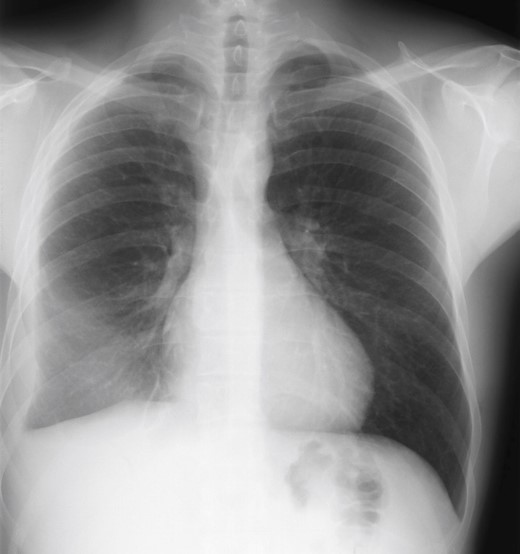

• Imagerie du Thorax - Technique et critère de qualité

• La radiographie standard du thorax